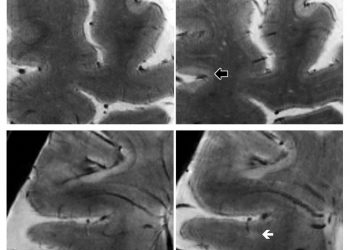

ЧИТАТЬ ВСЕ7Т МРТ в начале исследования (слева) и 1,5 года наблюдения (справа) у женщины с вторичным прогрессирующим РС, показывающим развитие двух...